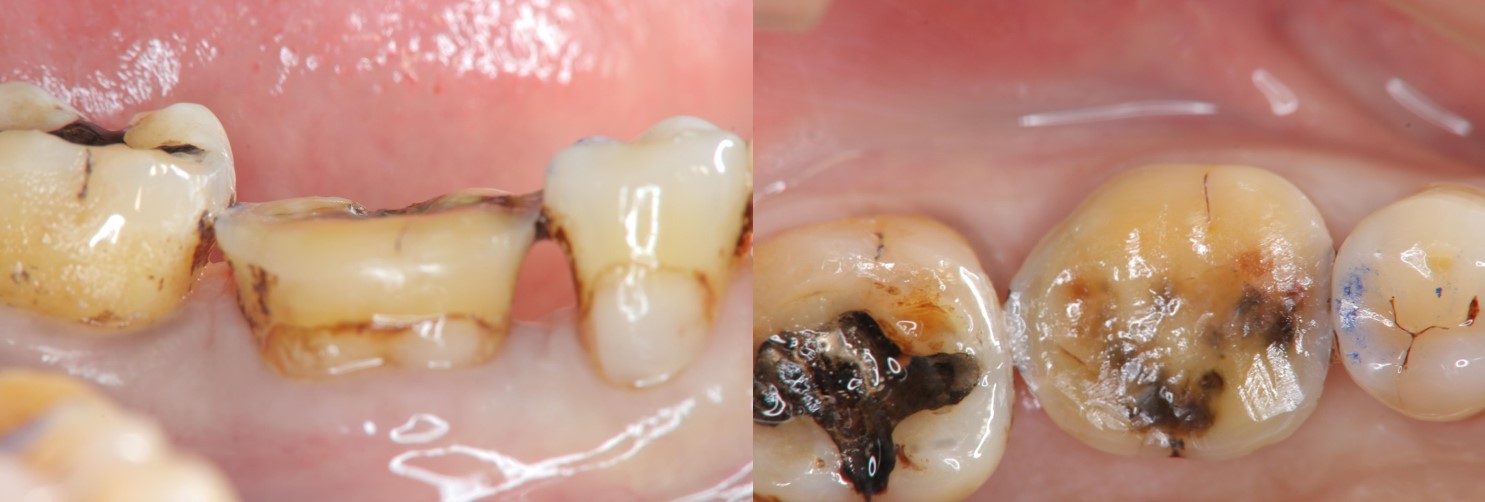

治療前,牙齒嚴重磨耗

治療前,牙髓仍未受侵犯

當磨耗破壞程度大,陶瓷冠塊體是根據蛀牙的窩洞量身訂做,不管是顏色、精密度都是最佳的選擇,因此是非常美觀與持久的填補窩洞材料與技術